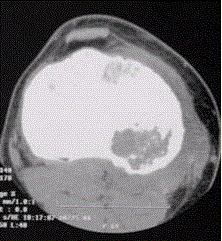

患者男,15岁。右膝X线平片和CT检查见下图。病变发生部位是A.骨端B.干骺端C.骨骺D.骨干E.关节腔

问题 患者男,15岁。右膝X线平片和CT检查见下图。 病变发生部位是

选项 A.骨端 B.干骺端 C.骨骺 D.骨干 E.关节腔

答案 C